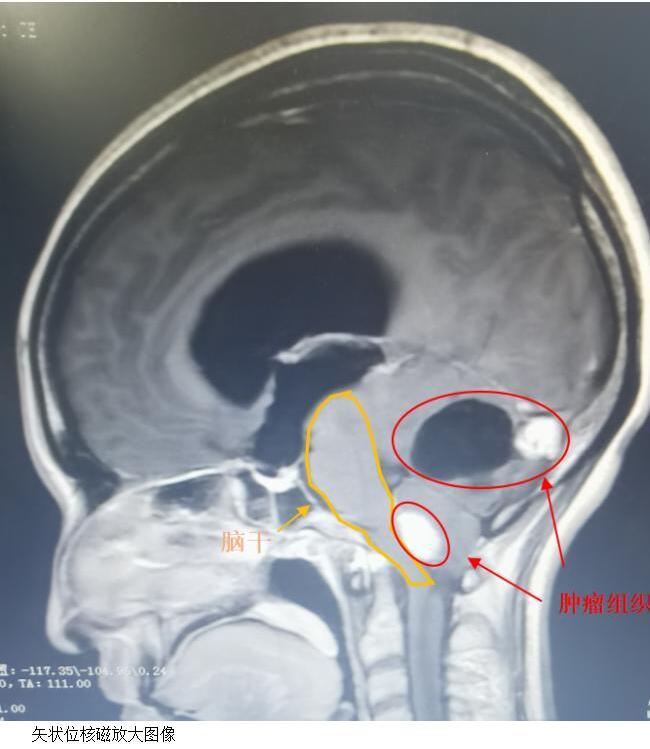

患者由于20余天进食不佳,入院体重仅35kg,虽然各项采血指标未见明显异常,但低体重和营养不良会对患者在麻醉药物代谢、耐受失血程度以及术后抗感染和恢复能力等方面带来非常不利的影响。除此之外,入院后所行头部增强磁共振影像显示的结果让大家更是倍感压力:小脑和脑干部位多达6处病变,分别位于双侧小脑半球和延髓背侧,肿瘤性质包括囊性、囊实结合和实性,实性肿瘤也意味着供血更为丰富,最大的肿瘤直径将近4cm。对患者影响最大的还是位于四脑室下方,延髓背侧的实性肿瘤,它是造成梗阻性脑积水和小脑扁桃体下疝的主要原因,而延髓更是心跳和呼吸等生命中枢的所在,稍有损伤,就会给患者带来致命和极其严重的后果。面对种种困难,赵振环主任团队没有退缩,凭借严谨的工作态度和丰富的治疗经验,在及时调整患者的生理和心理状态的同时,制定周密科学的手术方案:本次手术将延髓病变和右侧几个较大病变一次切除,左侧两个病变较小,距离中线较远,可动态观察。

2024年2月2日,在松北院区麻醉科和手术室的通力配合下,赵振环主任团队为患者实施了后正中入路肿瘤切除+后颅窝减压手术,按照预定方案成功将患者延髓背侧肿瘤和右侧小脑的三个肿瘤完整切除。术后患者意识清楚,四肢活动自如,出现一过性口齿不清和吞咽不良,三天后逐渐好转,术后14天出院时双眼视力及视野均较术前有明显改善,说话及吞咽功能已完全恢复,目前在家休息中,准备近日来院复查。术后病理显示:血管母细胞瘤。